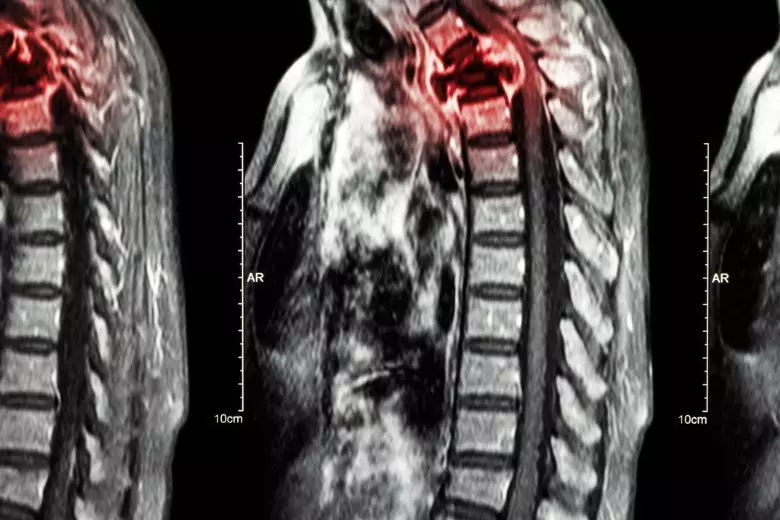

Wirbelsäulenmetastasen treten auf, wenn Krebszellen sich von ihrem ursprünglichen Tumorort ausbreiten und in die Wirbelsäule vordringen. Dies stellt eine häufige Komplikation bei fortgeschrittenen Krebserkrankungen dar. Auf dieser Seite geben wir Ihnen einen Überblick über die Erkrankung einschließlich moderner Behandlungsmöglichkeiten.